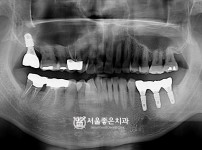

뼈이식 임플란트 2개 - 오스템 임플란트 / 상실치아, 많이 흔들리는 치아 발즉 임플란트

해당 게시물은 의료법 제56조에 의거하여 로그인 후 열람이 가능합니다.

구분 임플란트